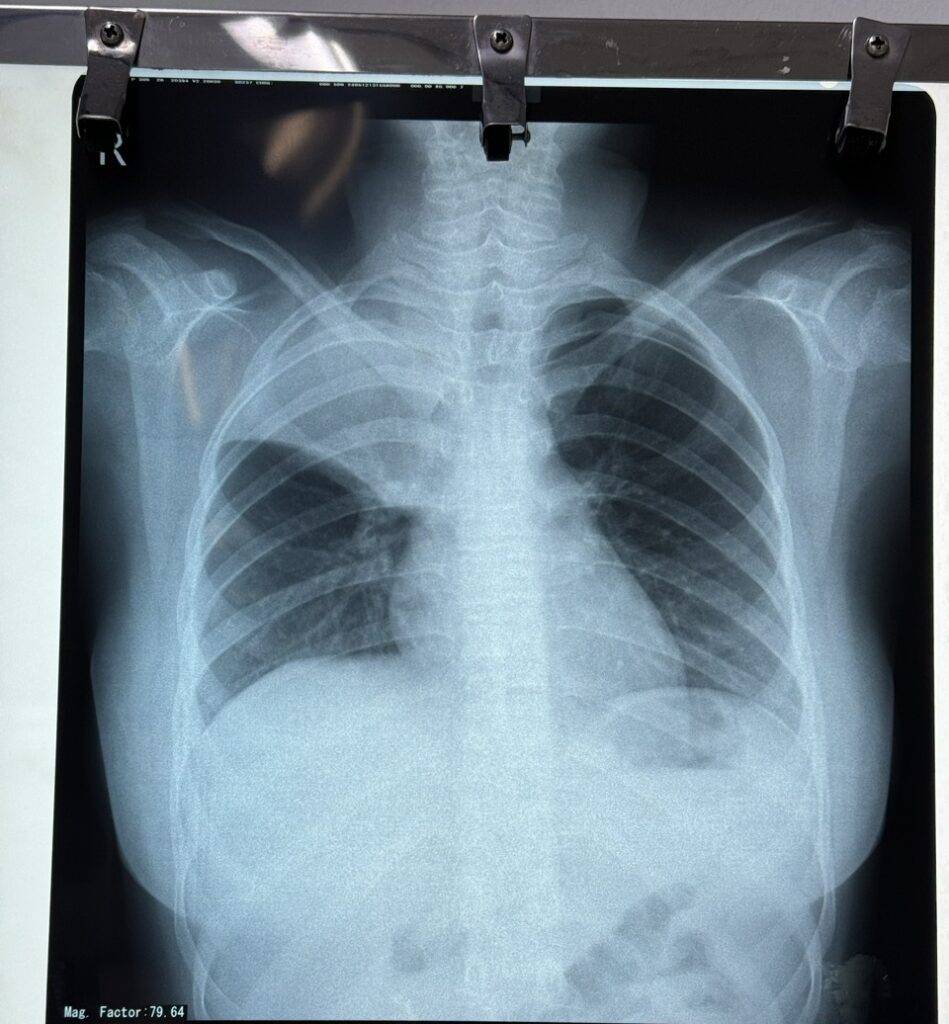

Sau khi thăm khám và thực hiện các cận lâm sàng cần thiết, kết quả X-quang phổi có hình ảnh đám mờ đồng nhất thùy trên phổi phải. Sau đó bé được chụp cắt lớp vi tính MSCT ngực ghi nhận kết quả: xẹp toàn bộ thùy trên phổi phải, kèm thâm nhiễm tạo đám mờ đồng nhất. Các xét nghiệm khác chưa ghi nhận bất thường.

Bệnh nhi được chẩn đoán: viêm phổi thùy đỉnh phổi phải.

Phim X – Quang trước (trái) và sau 06 ngày điều trị (phái).